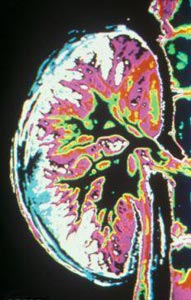

عضو هیات علمی دانشگاه علوم پزشکی جندی شاپور اهواز گفت: ادرار از کلیه وارد میزنای شده و سپس به مثانه منتقل می‌شود و در صورتی که ضایعه‌ای در کلیه موجب خون‌ریزی شود، خون با ادرار مخلوط شده و از بدن خارج می‌شود.